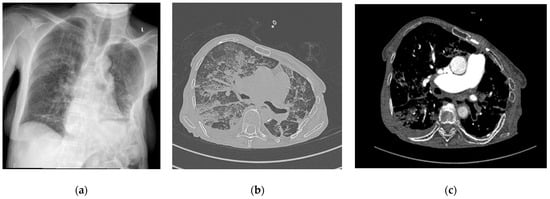

A 70-year-old female patient with right femoral neck fracture (FNF) garden type III returned to hospital after she refused surgical treatment 6 days ago. She was also suffering from pulmonary fibrosis (Figure 2a), rheumatoid arthritis (RA), chronic venous insufficiency (CVI), and high blood pressure (HBP) stage 1.

Figure 2.

(a) Chest X-ray at admission; (b) contrast-enhanced chest CT scan lung window after surgery; (c) contrast-enhanced chest CT scan soft tissue window after surgery. L—left side.

The same day, a cemented total hip arthroplasty was performed under intraspinal regional anesthesia with 10 mg of 0.5% heavy (H) marcaine and 5 µg of sufentanyl. While the cement was digitally applied into the femoral canal, the patient presented an emetic episode and tachycardia arrhythmia. After the surgery, she was agitated and desaturated. CT angiography (CTA) was requested that excluded pulmonary embolism (PE), describing bilateral bronchopneumonia outbreaks, pulmonary fibrosis associated with bronchiectasis, and pulmonary hypertension, with minimal pleurisy (Figure 2b,c).